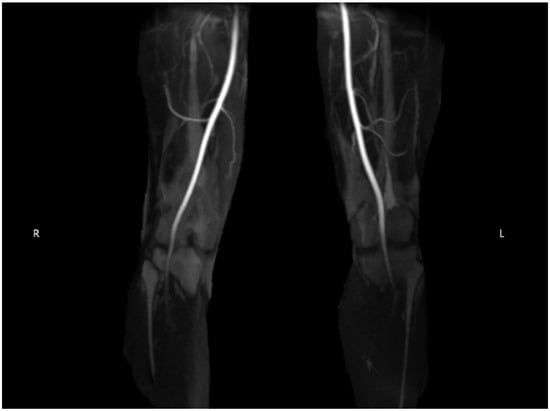

2.2. Diagnostic Testing

| Diagnosis | Compartment testing > 30 mmHg one minute after ceasing pain-provoking exercises. | CTA, MRA, or diagnostic angiography for confirmation of suspected PAES. |